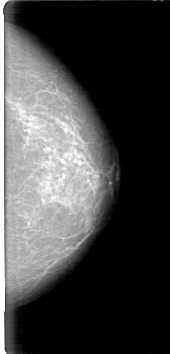

D_4027_1.LEFT_MLO

LEFT_MLO LINES 5386 PIXELS_PER_LINE 2746 BITS_PER_PIXEL 12 RESOLUTION 43.5 NON_OVERLAY